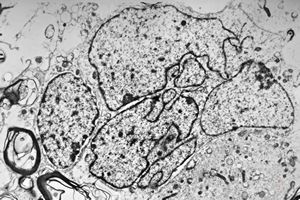

F,49y. | purulent meningitis- meningococcal v.s.

F,49y. | purulent meningitis- meningococcal v.s.

F,49y. | purulent meningitis- meningococcal v.s.